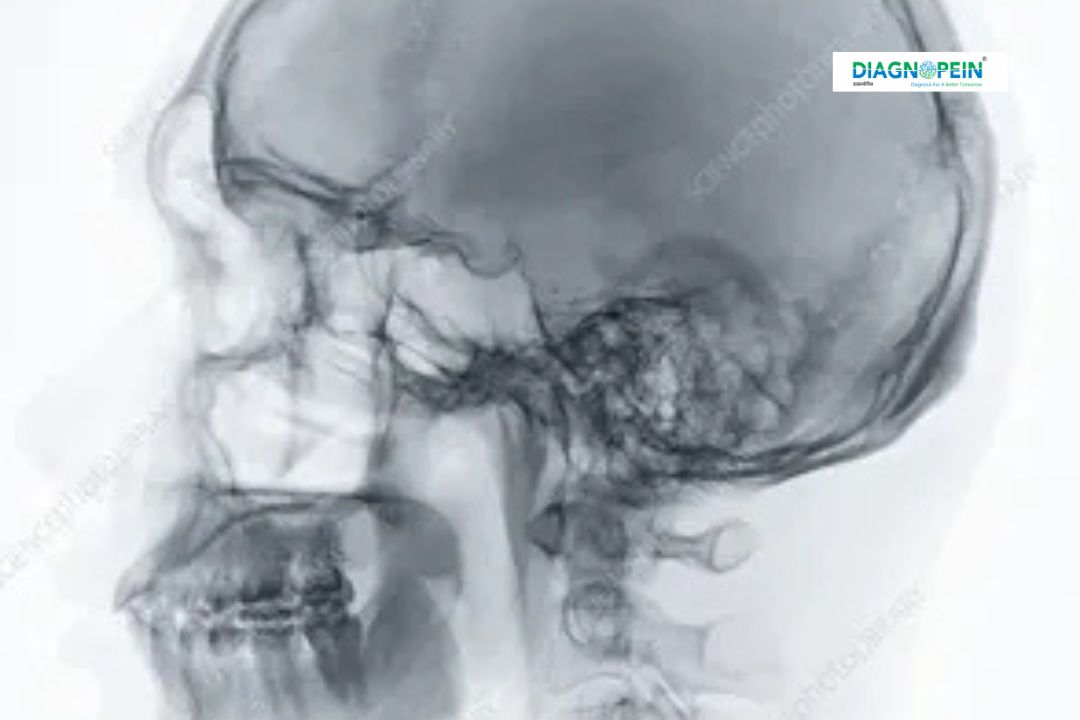

X-RAY SKULL AP/LATERAL X-RAY SKULL AP/LATERAL is a specialized diagnostic imaging test used to capture clear images of the skull bones from two different angles—Anteroposterior (AP) and Lateral views. This test helps doctors evaluate the structure of the skull, facial bones, and cranial vault. It is commonly recommended for patients with head injuries, chronic headaches, congenital skull abnormalities, or suspected fractures.

X-RAY SKULL AP/LATERAL plays a crucial role in detecting abnormalities related to the skull and brain casing. It helps doctors assess trauma-related injuries, bone lesions, infections, and deformities of cranial bones. Early detection through skull X-ray imaging can prevent complications and guide timely medical or surgical intervention.

This test is especially valuable in emergency cases involving head trauma, road accidents, or sports injuries. In routine clinical practice, it assists in diagnosing conditions such as sinus abnormalities, bone erosion, tumors, or congenital skull defects. X-RAY SKULL AP/LATERAL in Nashik is widely recommended due to its accessibility, affordability, and diagnostic accuracy.